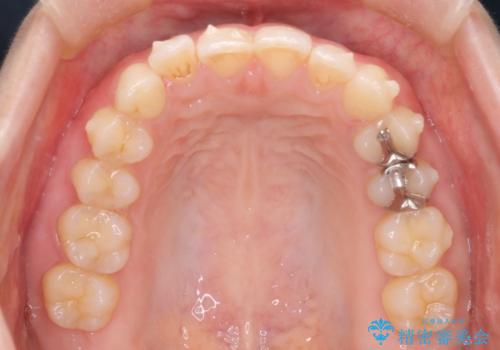

- 下顎前歯の叢生を主訴に来院されました。

臼歯関係の状態から下顎前歯一本の抜歯を行う治療計画を立て、インビザラインを使用して治療を行いました。

今回の抜歯ケースはインビザラインでも綺麗に治ります。